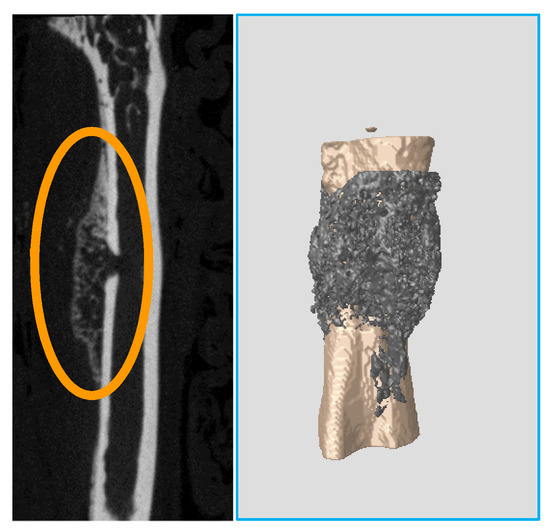

The cartilage covering the femoral head in hip joints mineralizes. It converts to a thick bony layer, losing the elastic properties of the chondral tissue (Figure 2). Osteoarthritis is installed. On the other hand, subchondral bone remains dense until the age of 80 weeks.

Figure 2.

(Left): 7 weeks (healthy) femoral head section. Outer cartilagenous layer is evident. (Right): 80 weeks (osteoarthritic) femoral head section. Cartilage has completely mineralized.